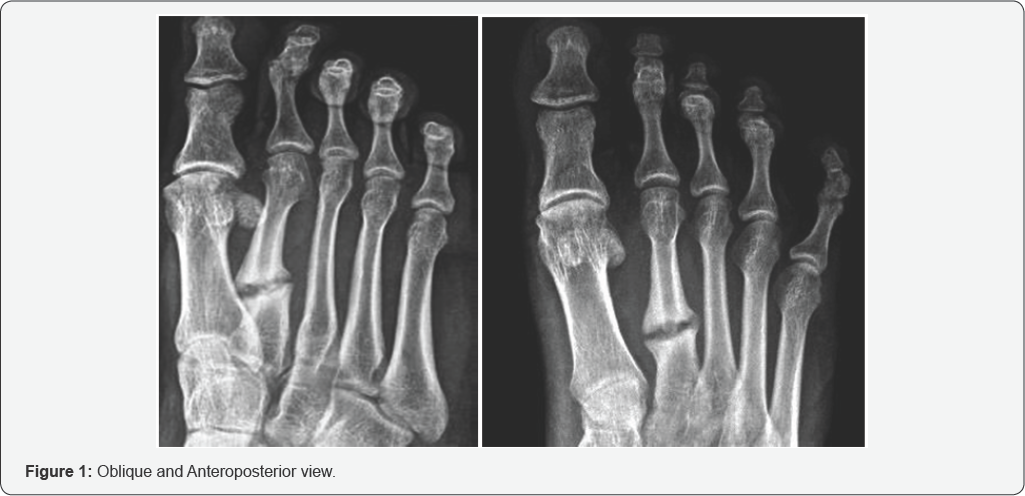

28 years old Man had accidental injury on 14 November 2014, open fracture of right second metatarsal was noted. He was treated at that time by orthopedic doctor. He was coming to me on November 2015, radiographic view shows Nonunion of second metatarsal fracture without open wound (Figure 1). After clinical evaluation of patient, we decided to go for fluoroscopic guided Activated PRP injection at nonunion site. We give multiple injection of PRP, we evaluate patient radiologically and clinically at 4 weeks interval up-to 6 months.